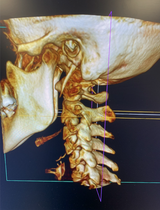

I-CAT Next Gen/FLX delivers an adjustable, large field of view (FOV) cone beam scan up to 17 x 23 cm for the widest range of applications. Advanced features include 3D reconstructions and a fast scan protocol to minimize patient exposure.

Improved Diagnostic Accuracy: CBCT provides three-dimensional (3D) images of the patient's anatomy, allowing for more accurate and detailed assessments of the area of interest.